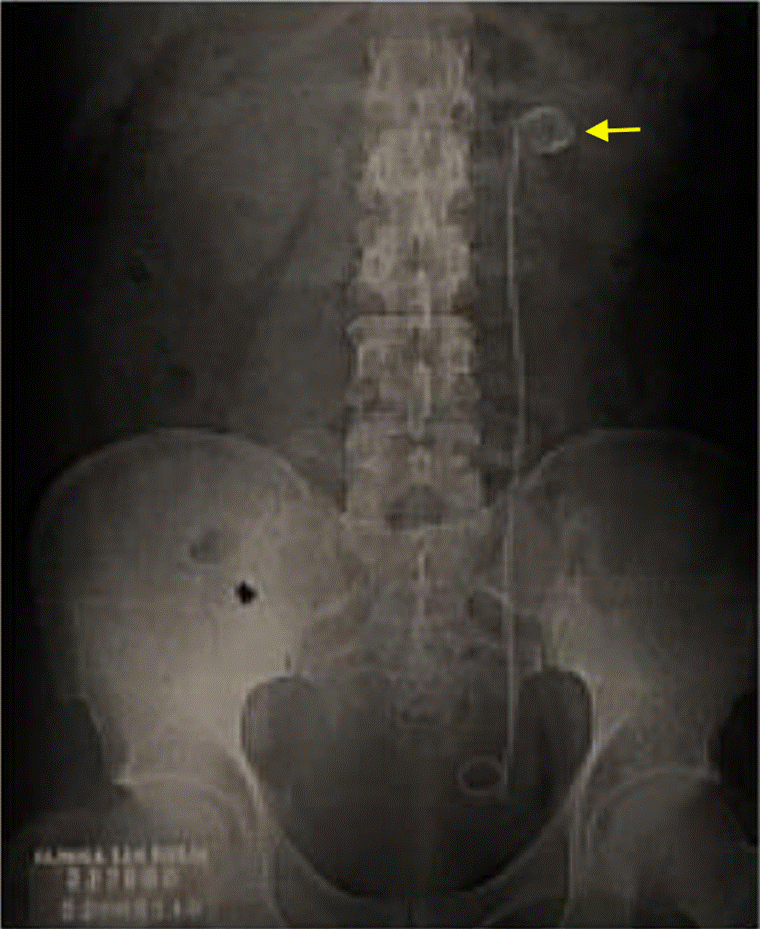

Durante su estancia hospitalaria, el paciente presentó expulsión espontánea de lito, con posterior descenso de azoados desde 2,48 mg/dL de creatinina al ingreso, hasta 1,5 mg/dL, por lo que fue llevado a implante de catéter doble J sin complicaciones. Luego de 21 días de antibiótico, los hallazgos radiológicos (Figura 4) mostraron una disminución de gas en el parénquima renal, por lo cual se le dio el alta hospitalaria y se definió el control para retiro de catéter doble J ambulatoriamente.

A partir de los hallazgos se confirma lo encontrado en otros estudios con respecto al logro de resultados exitosos a partir de un diagnóstico temprano y una combinación de intervenciones médicas y quirúrgicas oportunas, cuando sean necesarias, junto con un monitoreo meticuloso del progreso mediante evaluación radiológica secuencial, bien sea con radiografía como en el caso 1, o con tomografía como en el caso 2.